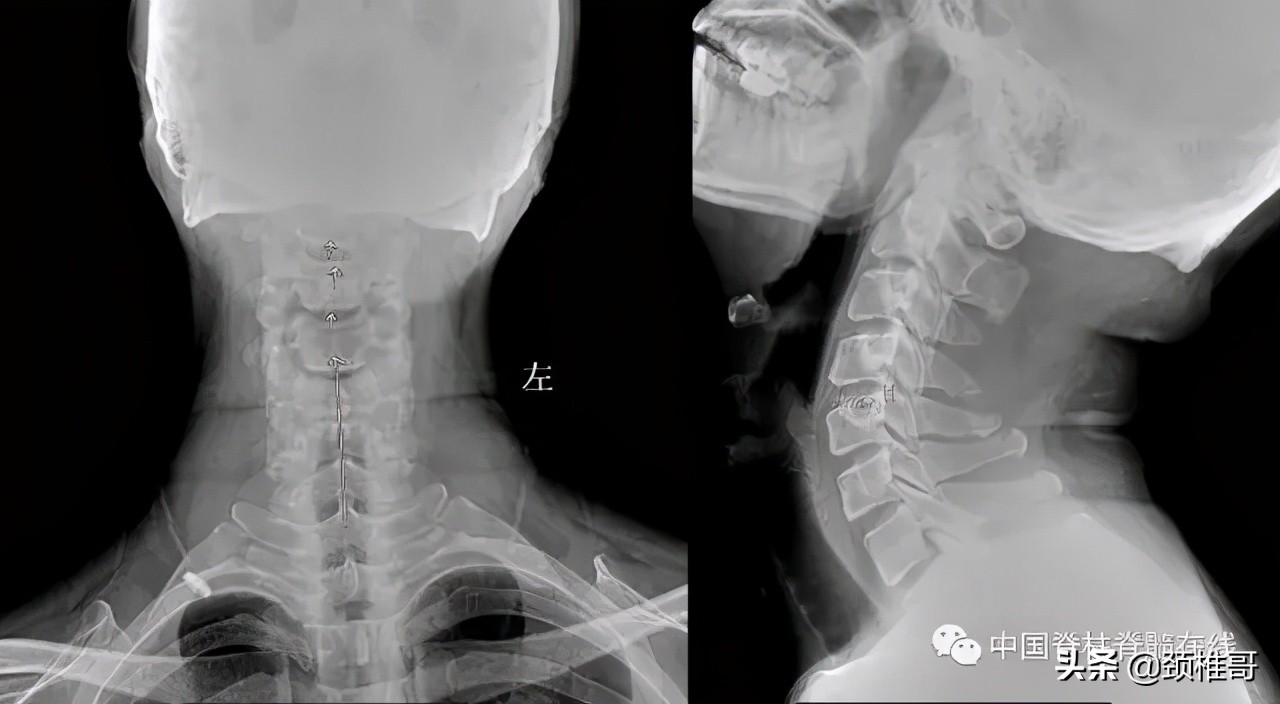

另外一个例子,这是一个头晕8年的病人,他的颈椎核磁共振显示,颈椎3-6各个节段之间的椎间盘退变膨出,局部有一些骨质增生,但没有明显的神经受压,横断面扫描显示颈椎周围肌肉有严重的退变表现;在X线检查时发现,棘突排列顺序不佳,颈4/5椎体之间有台阶,颈椎3-7各个节段之间夹角增大,都超过了11度;过屈位显示颈2-4椎出现了双边征,是旋转不稳的表现。这个病人的椎间盘虽然已经出现了退变、膨出,并发生了骨质增生,对硬膜囊产生了轻度压迫。但是其主要问题是椎间盘退变吗?不对,其主要问题还是多节段的椎间不稳,既有夹角增大,又有台阶,还有旋转。导致此病人头晕的主要原因还是肌肉和韧带的控制能力的下降所导致的。

正位显示椎体序列不佳、侧位显示颈椎4/5之间台阶状改变

过伸过屈侧位X线片显示多节段颈椎不稳

在椎间盘膨出、颈椎不稳基础上发生的代偿性增生